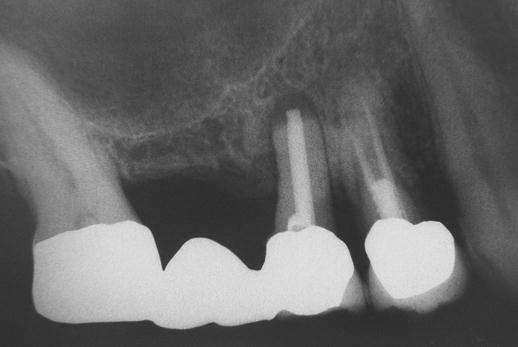

Při ztrátě molárů a premolárů v horní čelisti a jejich náhradě implantáty se často setkáváme s nedostatečnou

vertikální nabídkou kosti pod čelistní dutinou, často doprovázenou i nedostatečnou horizontální nabídkou a sníženou kvalitou kosti (v oblasti 2. premoláru v 50%, v oblasti moláru až v 80% případů nedostatečná kostní nabídka)